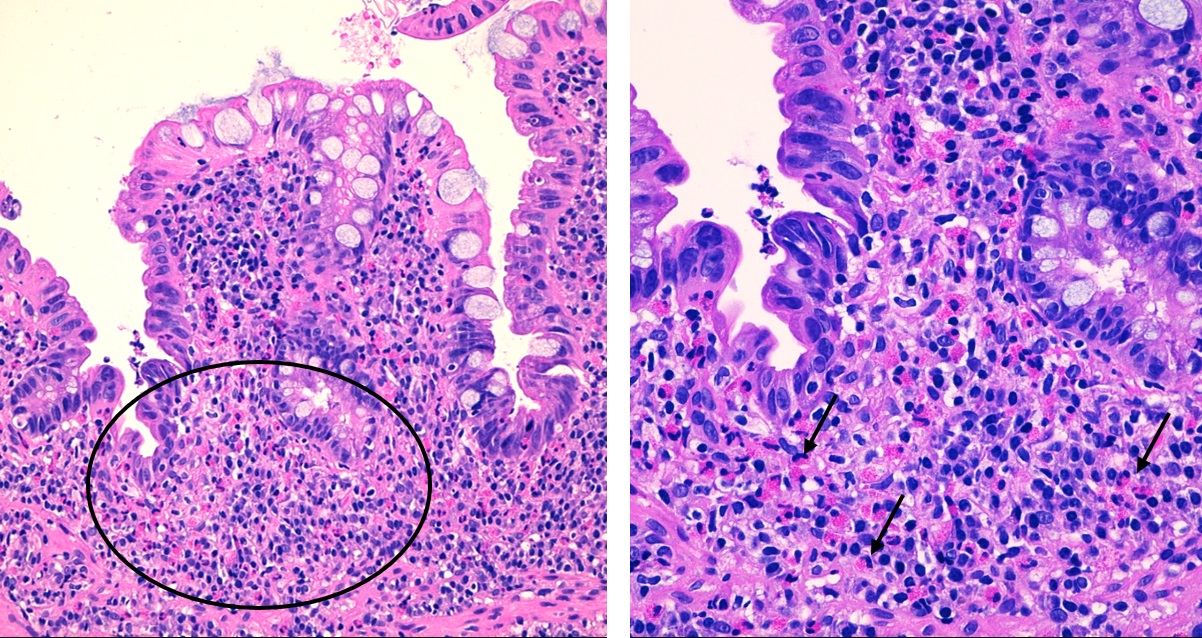

Niño de nueve años con antecedente de alergia a frutos secos, fruta y tomate natural, en seguimiento por Alergología. Consulta por dolor abdominal y deposiciones en número de 3-4 al día, de consistencia blanda, con sangre entremezclada, de dos meses de evolución. Niega ingesta de fármacos. No presenta astenia, pérdida de peso ni fiebre. En el estudio inicial destacan una eosinofilia periférica de 800/mm 3 y una calprotectina fecal de 1230 mg/kg. En el estudio de heces no se observan parásitos, bacterias o virus y la toxina de C. difficcile es negativa. Se repite calprotectina fecal al mes, con nuevo valor de 1930 mg/kg y analítica con eosinofilia de 800/mm 3. Se decide colonoscopia, que macroscópicamente es normal, pero el estudio anatomopatológico es compatible con colitis eosinofílica ( Fig. 2). Se inicia tratamiento con budesonida oral, con mejoría clínica.

El diagnóstico de colitis eosinofílica es de exclusión y requiere estudio endoscópico. En un alto porcentaje de casos no se observan hallazgos macroscópicos, lo cual pone de manifiesto la importancia de la toma de biopsias. En caso de estar presentes, destacan el eritema, el edema, las lesiones sobreelevadas y las aftas. A nivel histológico tiene importancia la densidad del infiltrado (expresado habitualmente como número de eosinófilos por campo de gran aumento) y son típicos los cambios regenerativos o degenerativos, la hiperplasia críptica, la atrofia vellositaria, los abscesos de eosinófilos y los signos de degranulación 11.